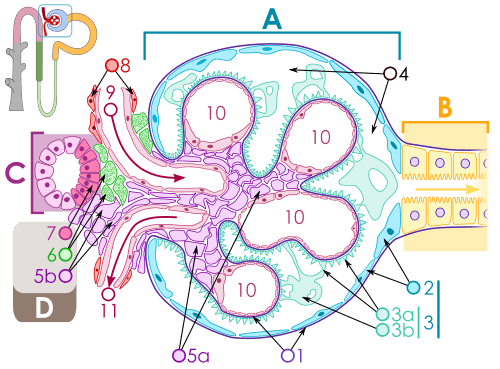

B. Glomerular basement membrane: 1. lamina rara interna 2. lamina densa 3. lamina rara externa

C. Podocytes: 1. enzymatic and structural proteins 2. filtration slit 3. diaphragma

The main function of the glomerulus is to filter plasma to produce glomerular filtrate, which passes down the length of the nephron tubule to form urine. The rate at which the glomerulus produces filtrate from plasma (the glomerular filtration rate) is much higher than in systemic capillaries because of the particular anatomical characteristics of the glomerulus. Unlike systemic capillaries, which receive blood from high-resistance arterioles and drain to low-resistance venules, glomerular capillaries are connected in both ends to high-resistance arterioles: the afferent arteriole, and the efferent arteriole. This arrangement of two arterioles in series determines the high hydrostatic pressure on glomerular capillaries, which is one of the forces that favour filtration to the Bowman's capsule.[6]

If a substance has passed through the glomerular capillary endothelial cells, glomerular basement membrane, and podocytes, then it enters the lumen of the tubule and is known as glomerular filtrate. Otherwise, it exits the glomerulus through the efferent arteriole and continues circulation as discussed below and as shown on the picture.

The structures of the layers determine their permeability-selectivity (permselectivity). The factors that influence permselectivity are the negative charge of the basement membrane and the podocytic epithelium, and the effective pore size of the glomerular wall (8 nm). As a result, large and/or negatively charged molecules will pass through far less frequently than small and/or positively charged ones.[7] For instance, small ions such as sodium and potassium pass freely, while larger proteins, such as hemoglobin and albumin have practically no permeability at all.

Capillaries of the glomerulus are lined by endothelial cells. These contain numerous pores (called fenestrae) 50–100 nm in diameter.[4] Unlike those of other capillaries with fenestrations, these are not spanned by diaphragms.[4] These pores allow for the free filtration of fluid, plasma solutes and protein. However they are not large enough that red blood cells can be filtered.

The glomerulus has a basement membrane consisting mainly of laminins, type IV collagen, agrin and nidogen, which are synthesized and secreted by both endothelial cells and podocytes. These form a membrane 250–400 nm in thickness, which is thicker than basement membranes in other types of tissue. The effects of mutations in the constituents of the glomerular basement membrane suggest that it plays a role in the permeability and selectivity of the filtration barrier to large molecules, such as albumin.[5]

The side of the basement membrane that faces outwards from the capillary is lined with folds called podocytes. These are themselves lined with folds of cytoplasm called foot processes, or pedicles.[4] These control the filtration of proteins from the capillary lumen into Bowman's space. The space between adjacent podocyte foot processes is spanned by a slit diaphragm formed by several proteins including podocin and nephrin. In addition, foot processes have a negatively charged coat (glycocalyx) that limits the filtration of negatively charged molecules, such as serum albumin.

The space between the cells of a glomerulus is occupied by intraglomerular mesangial cells. They are not part of the filtration barrier but are specialized pericytes that participate indirectly in filtration by contracting and reducing the glomerular surface area, and therefore filtration rate, in response mainly to stretch.